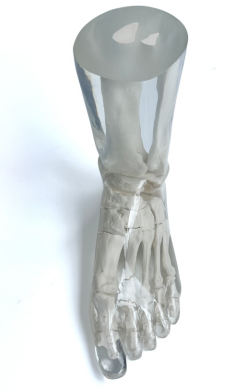

成人腿部模體,用于 X 射線(xiàn) CT 和超聲波的成人腿部(肌肉)模型是一種基于人類(lèi)男性腿部平均解剖結(jié)構(gòu)設(shè)計(jì)的逼真模型。它具有所有基本的骨骼和

軟組織特征,使其成為學(xué)習(xí)、研究和測(cè)試醫(yī)學(xué)成像設(shè)備的理想工具。 模體可用于研究不同方向和定位技術(shù)的多種診斷性 X 射線(xiàn) CT 和超聲程序。根據(jù)

要求,該產(chǎn)品可以根據(jù)不同的病理進(jìn)行定制,也可以用于特定的培訓(xùn)應(yīng)用。 模體尺寸:965.2 x 254 x 177.8 毫米,重量:12kg(約)